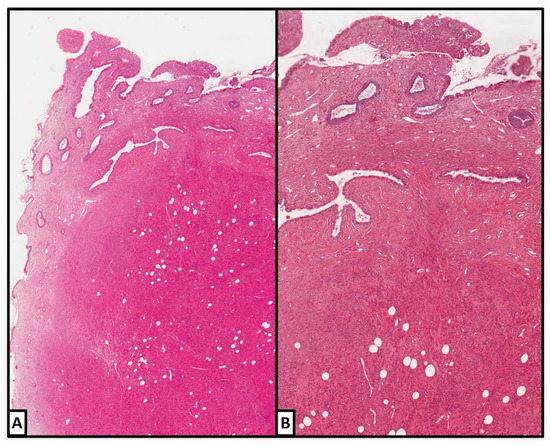

3.1. Our Case Series

3.1.1. Case 1

3.1.2. Case 2

3.1.3. Case 3

3.1.4. Case 4

3.1.5. Case 5